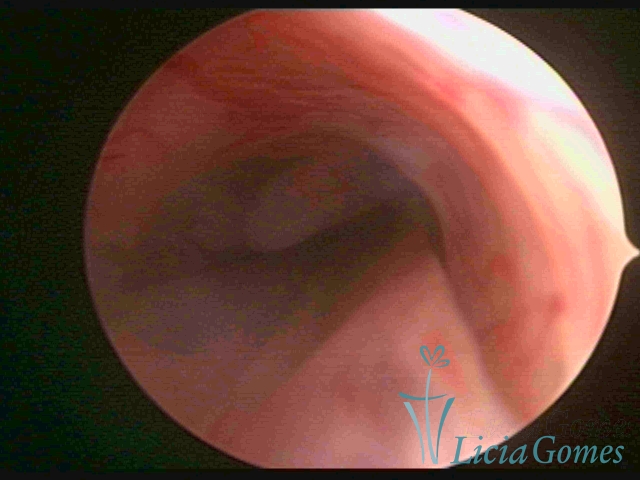

PÓLIPOS ENDOCERVICAIS

São tumores benignos, resultantes da proliferação focal reativa aos processos inflamatórios ou à situações de hiperestrogenismo, e podem ter sésseis (com a base de implantação larga) ou pediculados do epitélio.